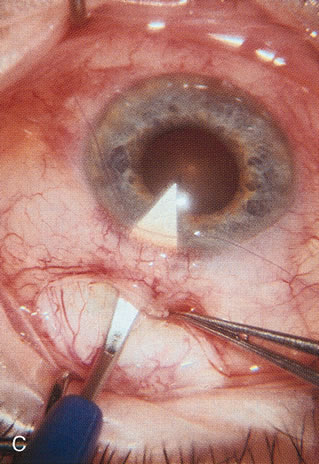

Fig. 7. Phacotrabeculectomy adjacent to a failed filter in cataractous eye. The ability to combine small-incision cataract extraction with trabeculectomy all through the same incision adjacent to the failed filter allows the surgeon to work in a familiar superior area. Avoiding incisions into the existing bleb decreases conjunctival buttonholes, hypotony, operating room time, and subconjunctival bleeding. A. Appearance of failed bleb with exposure of superior temporal quadrant gained with a corneal traction suture. B. Prepare a limbus-based conjunctival flap and a scleral flap. C. This bleb is at high risk to fail again justifying the need for MMC, 0.2 mg/cc applied on a pledget for 4 minutes. D. Insert the keratome and perform phacotrabeculectomy in the usual fashion.